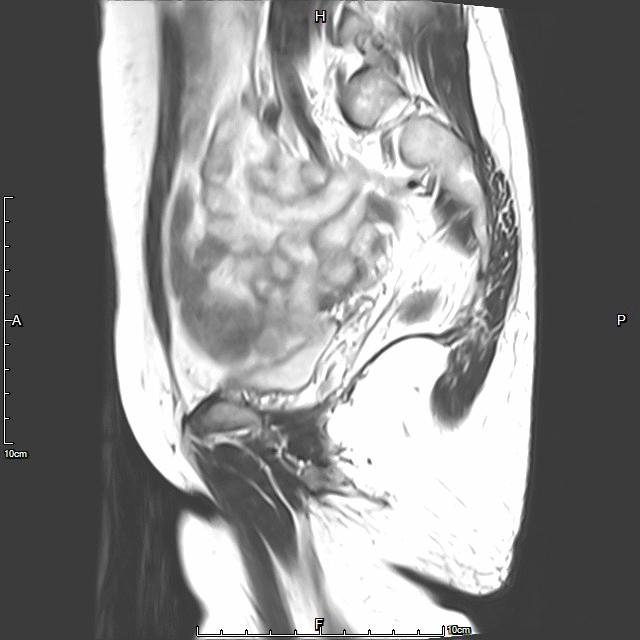

- 术前MRI显示子宫明显增大,病灶主要位于子宫前壁

术前MRI显示子宫明显增大,病灶主要位于子宫前壁

- 术前MRI检查显示子宫明显增大。

术前MRI检查显示子宫明显增大

- 术前彩超、磁共振检查显示子宫明显增大,子宫前壁可见弥漫型子宫腺肌症病灶,合并粘膜下、肌壁间子宫肌瘤。

矢状位